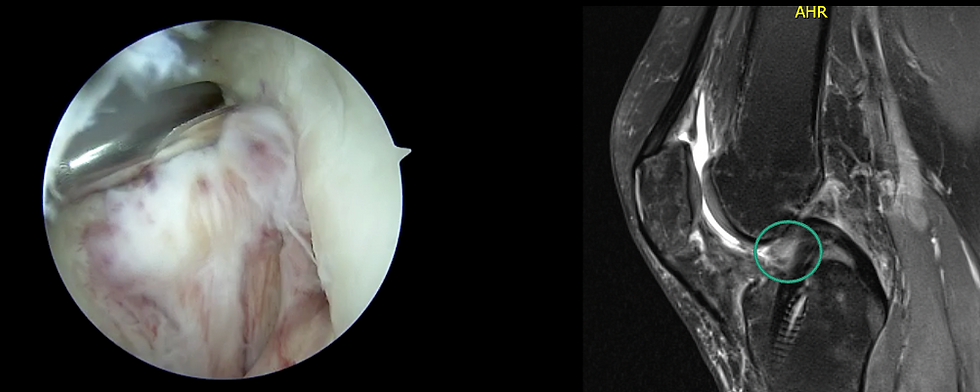

Cartilage Restoration Procedures

Cartilage damage in the knee can cause pain, swelling, and stiffness. Since cartilage doesn’t heal well on its own, procedures like microfracture, cartilage grafting, or cell-based therapies (ACI) can help regenerate new cartilage and protect the joint. These treatments are usually recommended for younger patients with localized cartilage damage.